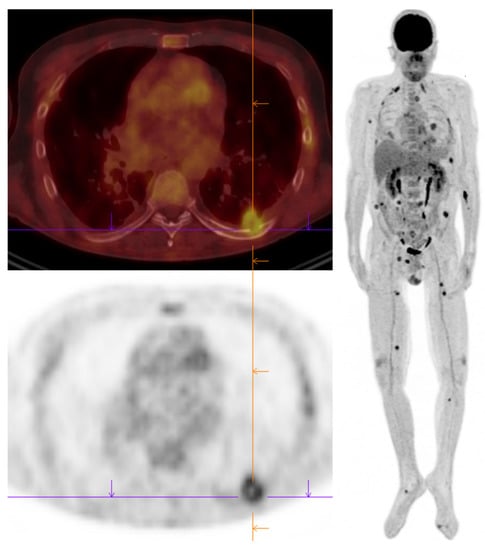

- Chamilos, G.; Macapinlac, H.A.; Kontoyiannis, D.P. The use of 18F-fluorodeoxyglucose positron emission tomography for the diagnosis and management of invasive mould infections. Med. Mycol. 2008, 46, 23–29. [Google Scholar] [CrossRef]

- Leroy-Freschini, B.; Treglia, G.; Argemi, X.; Bund, C.; Kessler, R.; Herbrecht, R.; Imperiale, A. 18F-FDG PET/CT for invasive fungal infection in immunocompromised patients. QJM 2018, 111, 613–622. [Google Scholar] [CrossRef]

- Fernandez-Cruz, A.; Lewis, E.R.; Kontoyiannis, D.P. How long do we need to treat an invasive mold disease in hematology patients? Factors influencing duration of therapy and future questions. Clin. Infect Dis. 2020, 71, 685–692. [Google Scholar] [CrossRef]